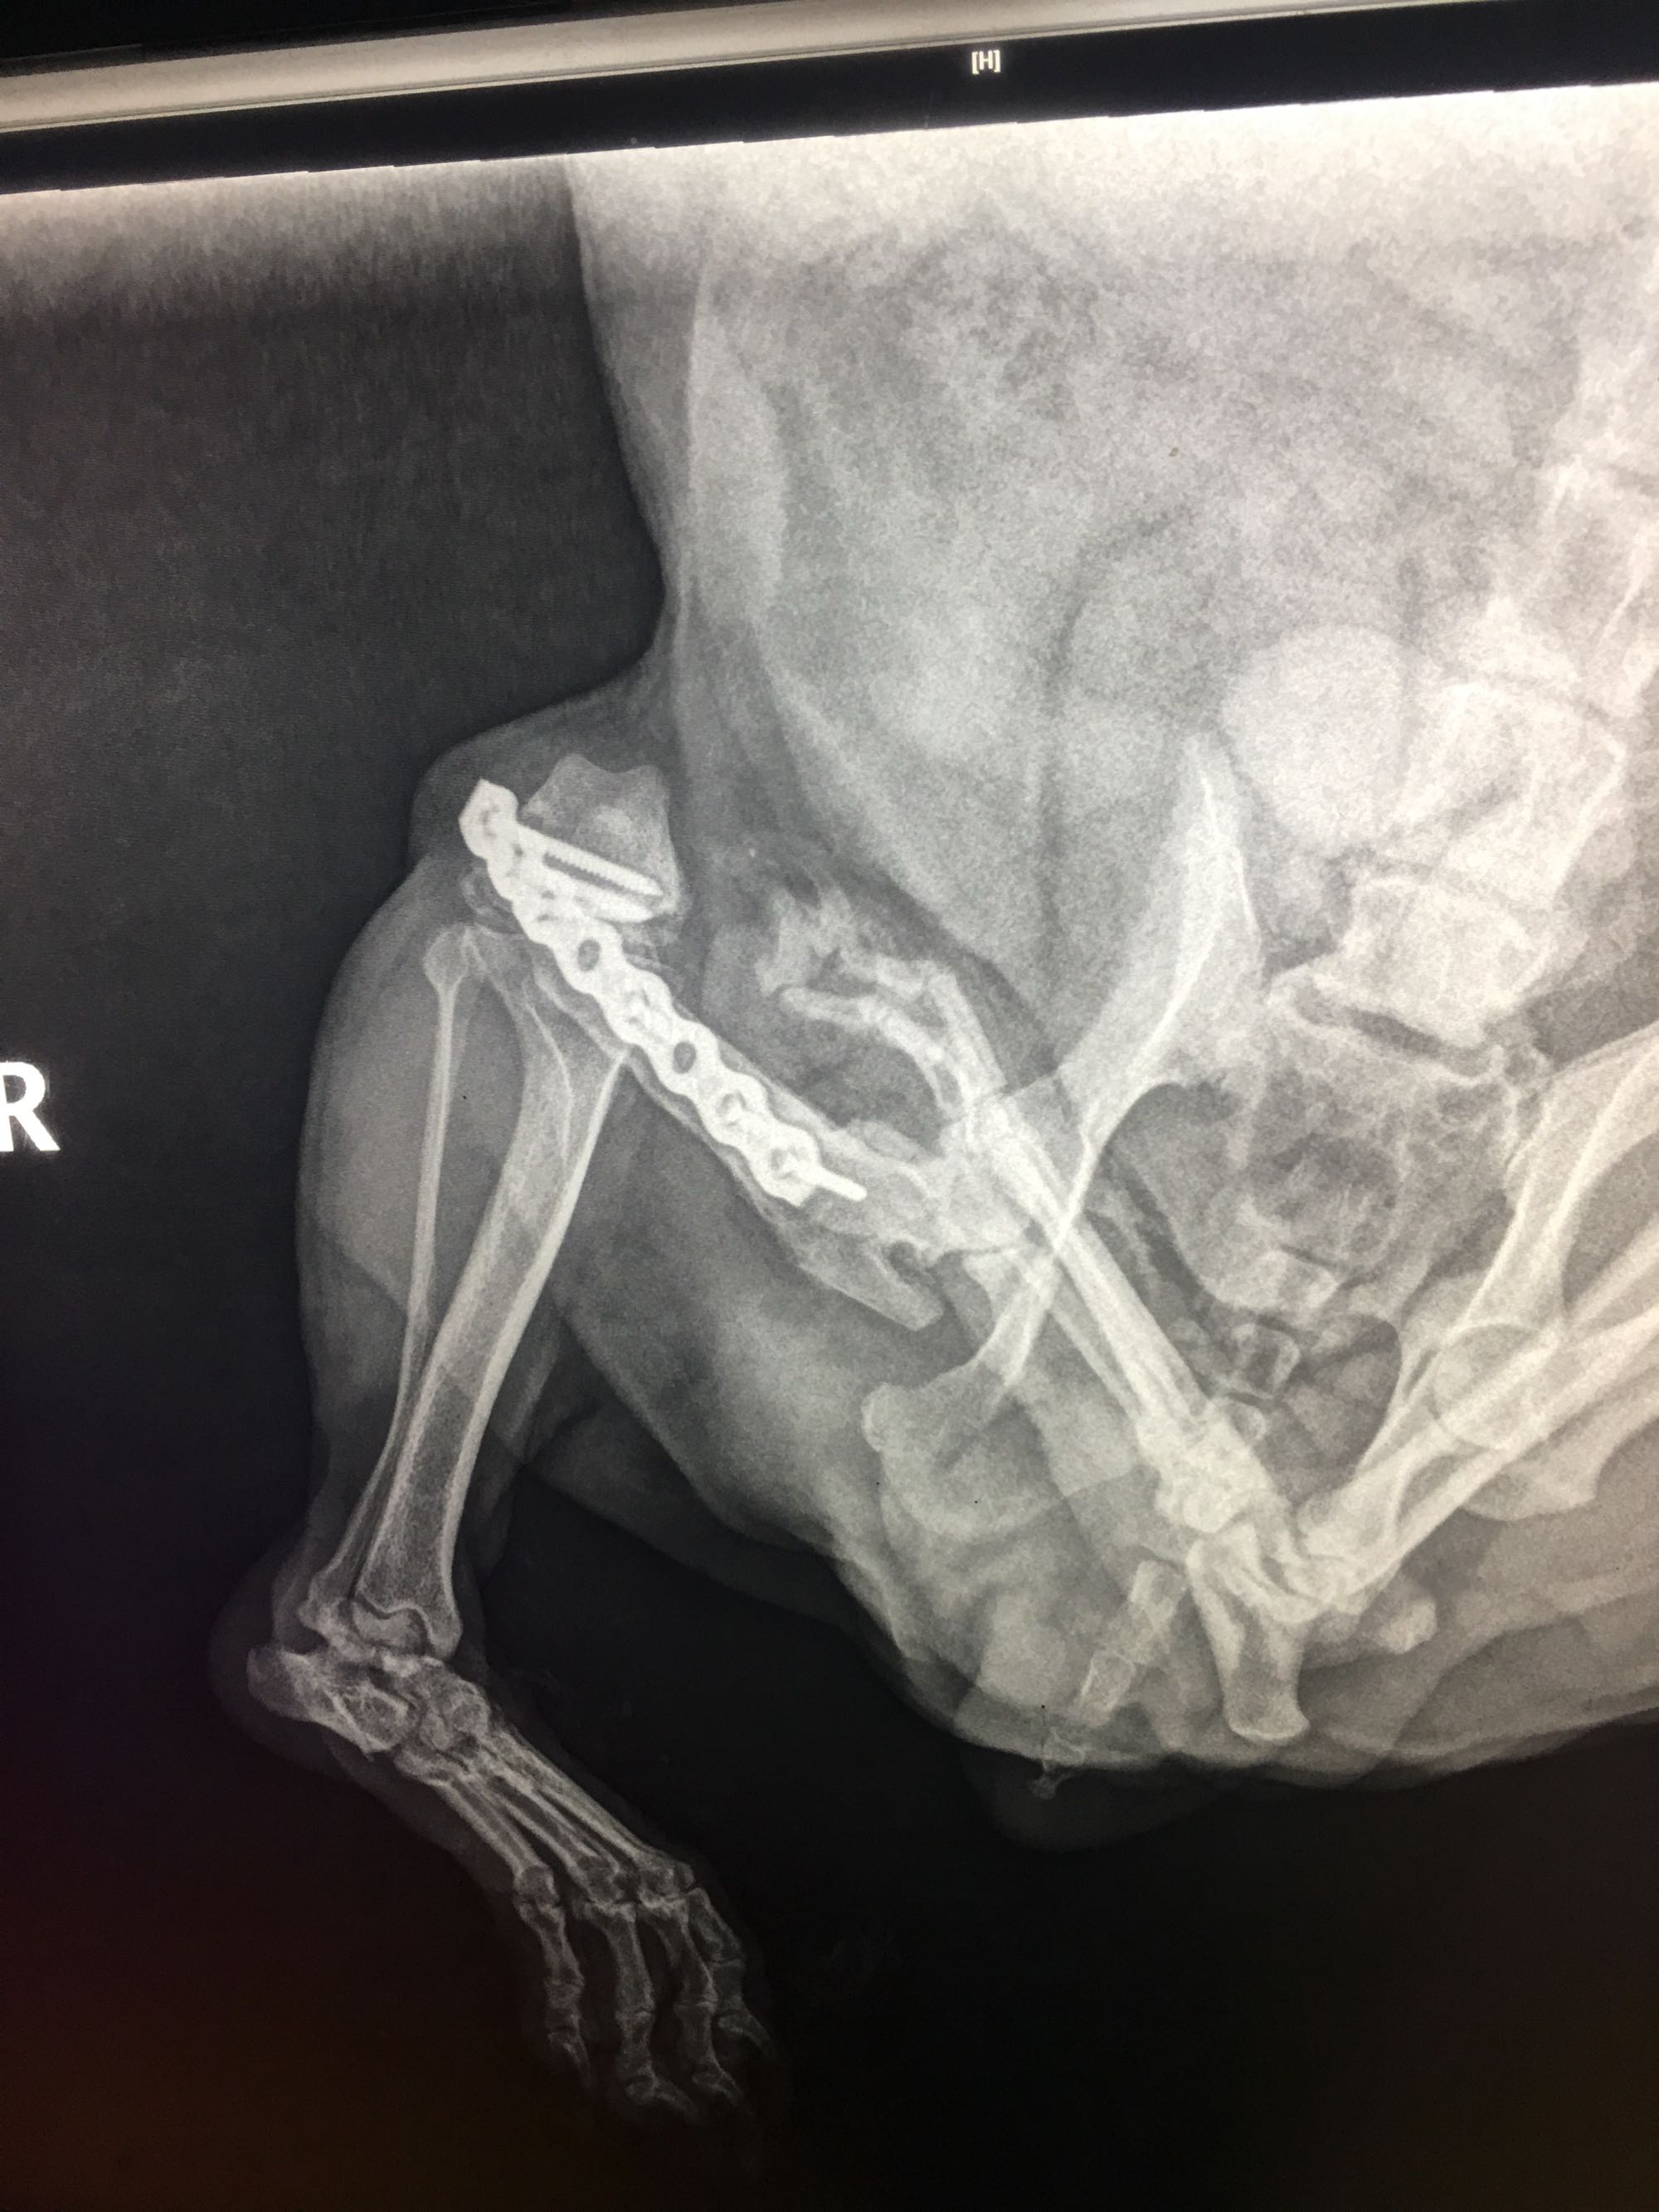

长沙医学院第一附属医院门口发现一只流浪狗,疑似雪纳瑞。左后腿受伤了,有爱狗人士领养吗?!

我们给狗狗拍了X线,居然做过手术了。但不知道为什么被没人管。